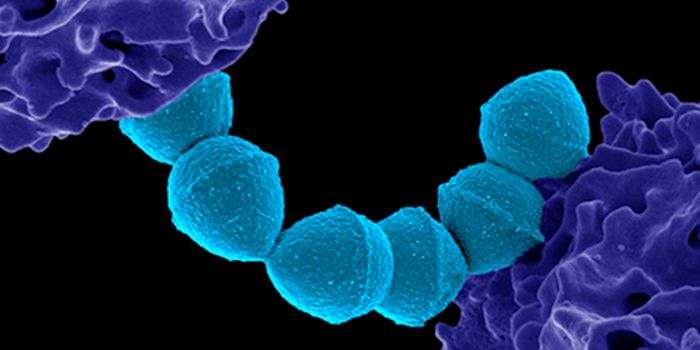

MAR 05, 2023MicrobiologyEstimates vary, but Streptococcus pyogenes infections may be responsible for the deaths of over 500,000 people every yea ...